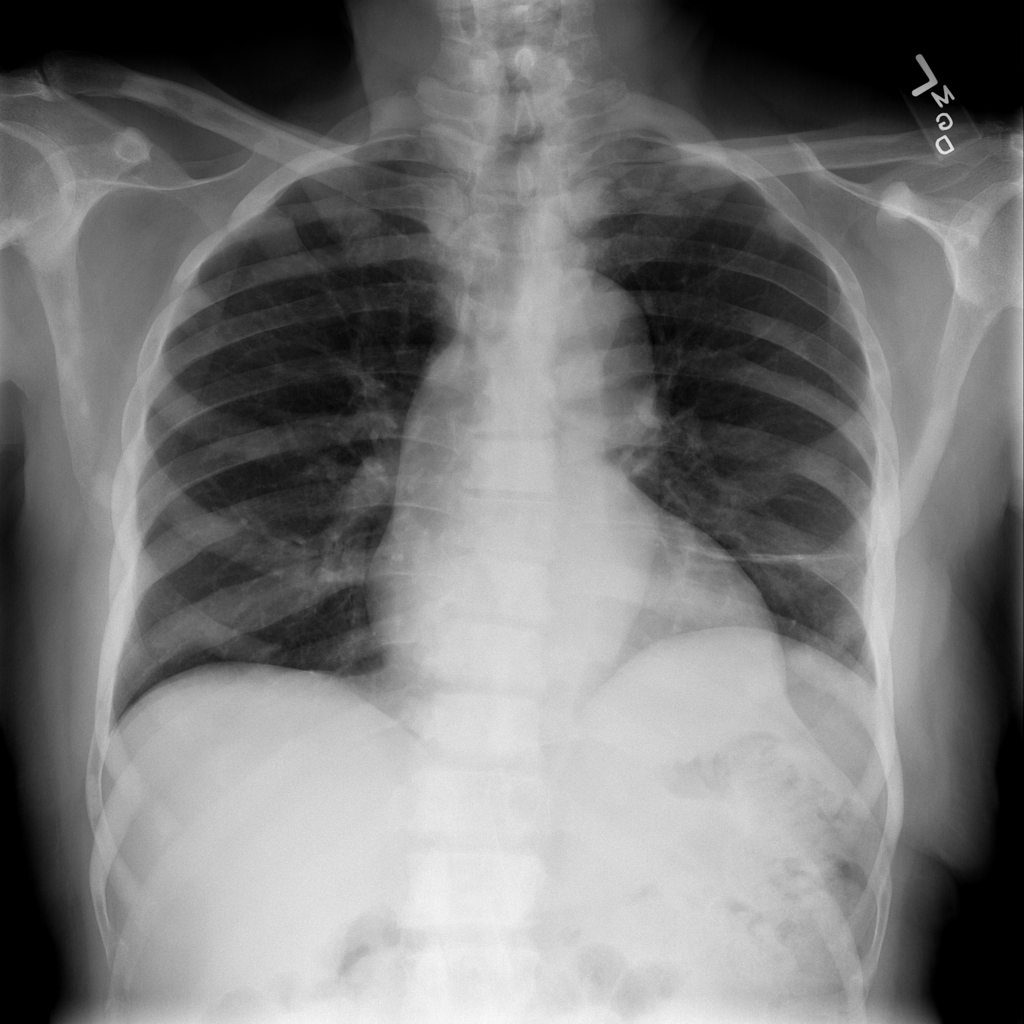

PAT-86C8 · IMG-006Atelectasis

PAT-86C8 · IMG-006

PA